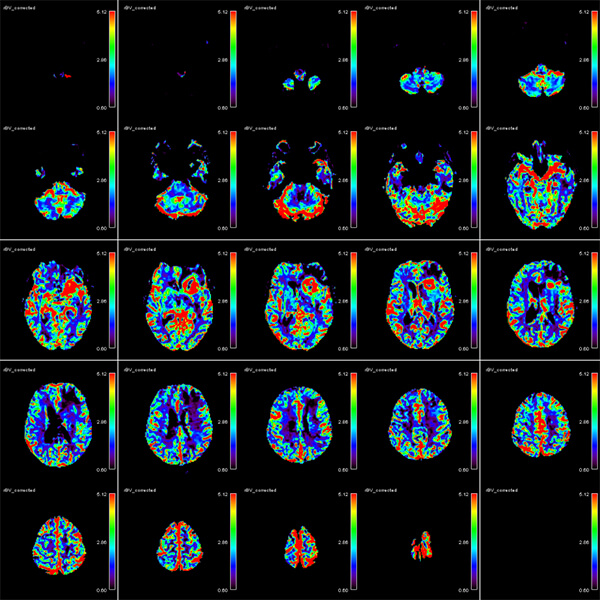

- Ειδικές τεχνικές state-of-the-art (Λειτουργική / Πολυπαραμετρική MRI, Φασματοσκοπία, Δεσμιδογραφία, Δυναμικές Αγγειογραφίες, Νευρογράφημα, Μελέτη Ροής ΕΝΥ)

- Συνδυασμός των ειδικών τεχνικών με ανατομικές εικόνες υψηλής ευκρίνειας, ο οποίος δίνει σημαντικές επιπρόσθετες πληροφορίες για τον χαρακτηρισμό του ιστού (αριθμό των κυττάρων, αιματική ροή και μεταβολική δραστηριότητα)

- Ειδικές τεχνικές Diffusion (multiple b value DWI, IVIM)

- Perfusion (τεχνικές DSC, DCE, ALS)